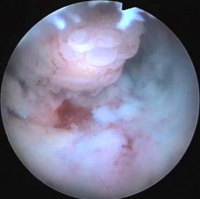

镜下的子宫内膜息肉

镜检:子宫内膜息肉由子宫内膜组成,表面被覆一层立方上皮或低柱状上皮。息肉中间部分形成纤维性纵轴,其内含有血管

2、镜检:子宫内膜息肉由子宫内膜组成,表面被覆一层立方上皮或低柱状上皮。息肉中间部分形成纤维性纵轴,其内含有血管。由于蒂部狭窄,血液供应减少,息肉极易变性。最易发生息肉血管内血栓形成,因瘀血而变成深紫色,常在顶端开始发生坏死,最后可能腐崩而脱落。